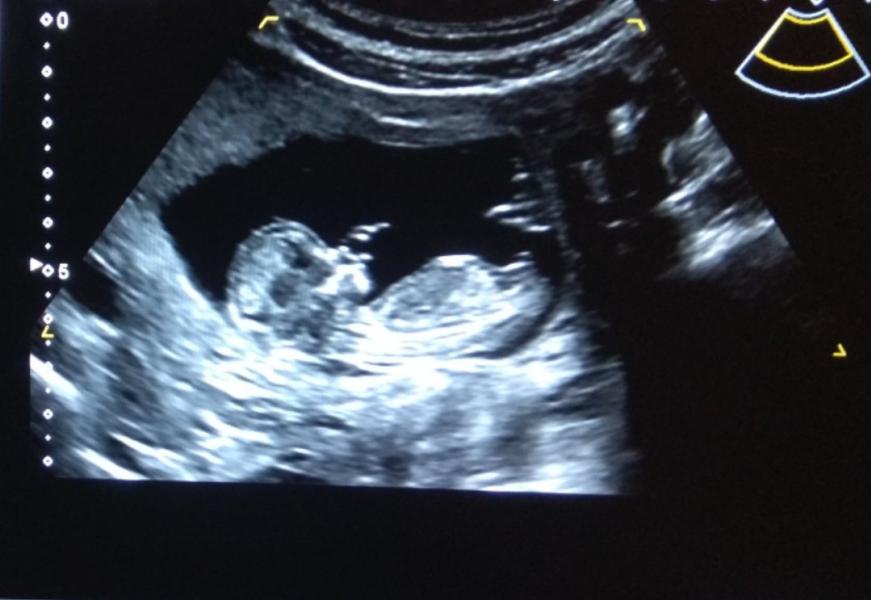

Первого октября тоже иду на УЗИ на 13 неделе! 🙈🙉🙊 Красотульки! 😍